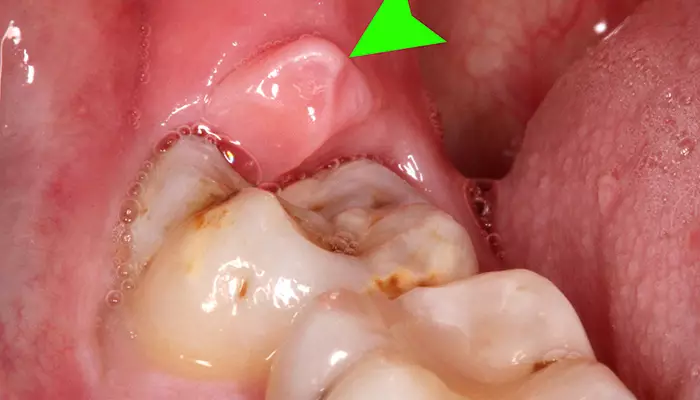

دندانهای عقل آخرین دندانهایی هستند که معمولاً در سنین بالا ظاهر میشوند. دندانپزشک در بیشتر مواقع دندان عقل را به دلیل جاگیری نامناسب و کوچکی فک میکشد. عفونت دندان عقل یا پری کورونیت، معمولاً به دلیل رعایت نکردن بهداشت دهان و دندان ایجاد میشود. این دندانها آخرین دندانهای فک هستند؛ بنابراین دسترسی به آنها و تمیز کردنشان به سختی انجام میشود. همچنین گاهی اوقات، دندان عقل زیر لثه گیر میکند و همین باعث عفونت دندان عقل میشود.

برای جلوگیری از عفونت دندان عقل و مشکلات مربوط به آن، با ظهور اولین نشانههای رشد دندان عقل به دندانپزشک مراجعه کنید. دندانپزشک با بررسی وضعیت قرارگیری دندان عقل، تعیین میکند که آیا نیاز به کشیدن و جراحی دندان عقل دارید یا خیر.

تصویری از عفونت دندان عقل